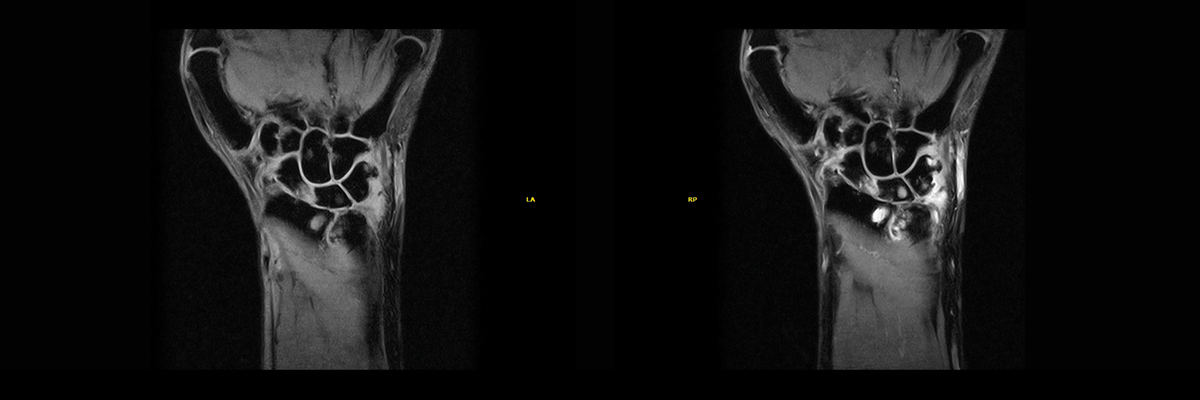

The Dynamic MRI Analysis Package available for all Esaote MRI systems ensures efficiency when it comes to the timely diagnosis and treatment of rheumatic disease and confirms Esaote’s commitment to patient care. It is a more comprehensive image analysis toolkit ideal also for rheumatologists as it comes with a pool of sensitive wrist sequences for acquiring high-resolution image sequences for better contrast of bone edema. In addition, the kit includes a contrast uptake analysis tool for disease activity evaluation and therapy follow-up and a wrist positioner for exam repetitions.

Image analysis tool for contrast uptake measurements

What it does:

- Uses 2 dynamic sequences (SE and GE).

- Takes images every few seconds at chosen intervals > Image co-registration algorithm for best alignment of images.

- Allows the user to define the place for measurements, region of interest (ROI) size and position creating a graph of the contrast uptake in the ROI over time.

- Documentation: exports the graph, related images RE and EER - Images in standard DICOM and jpeg (for Windows compatibility) - Graph in bitmap (filename.bmp) and .csv format.

- Saves images and graphs in the patient database for follow-up, for example when confronting pre- and post-treatment situations.